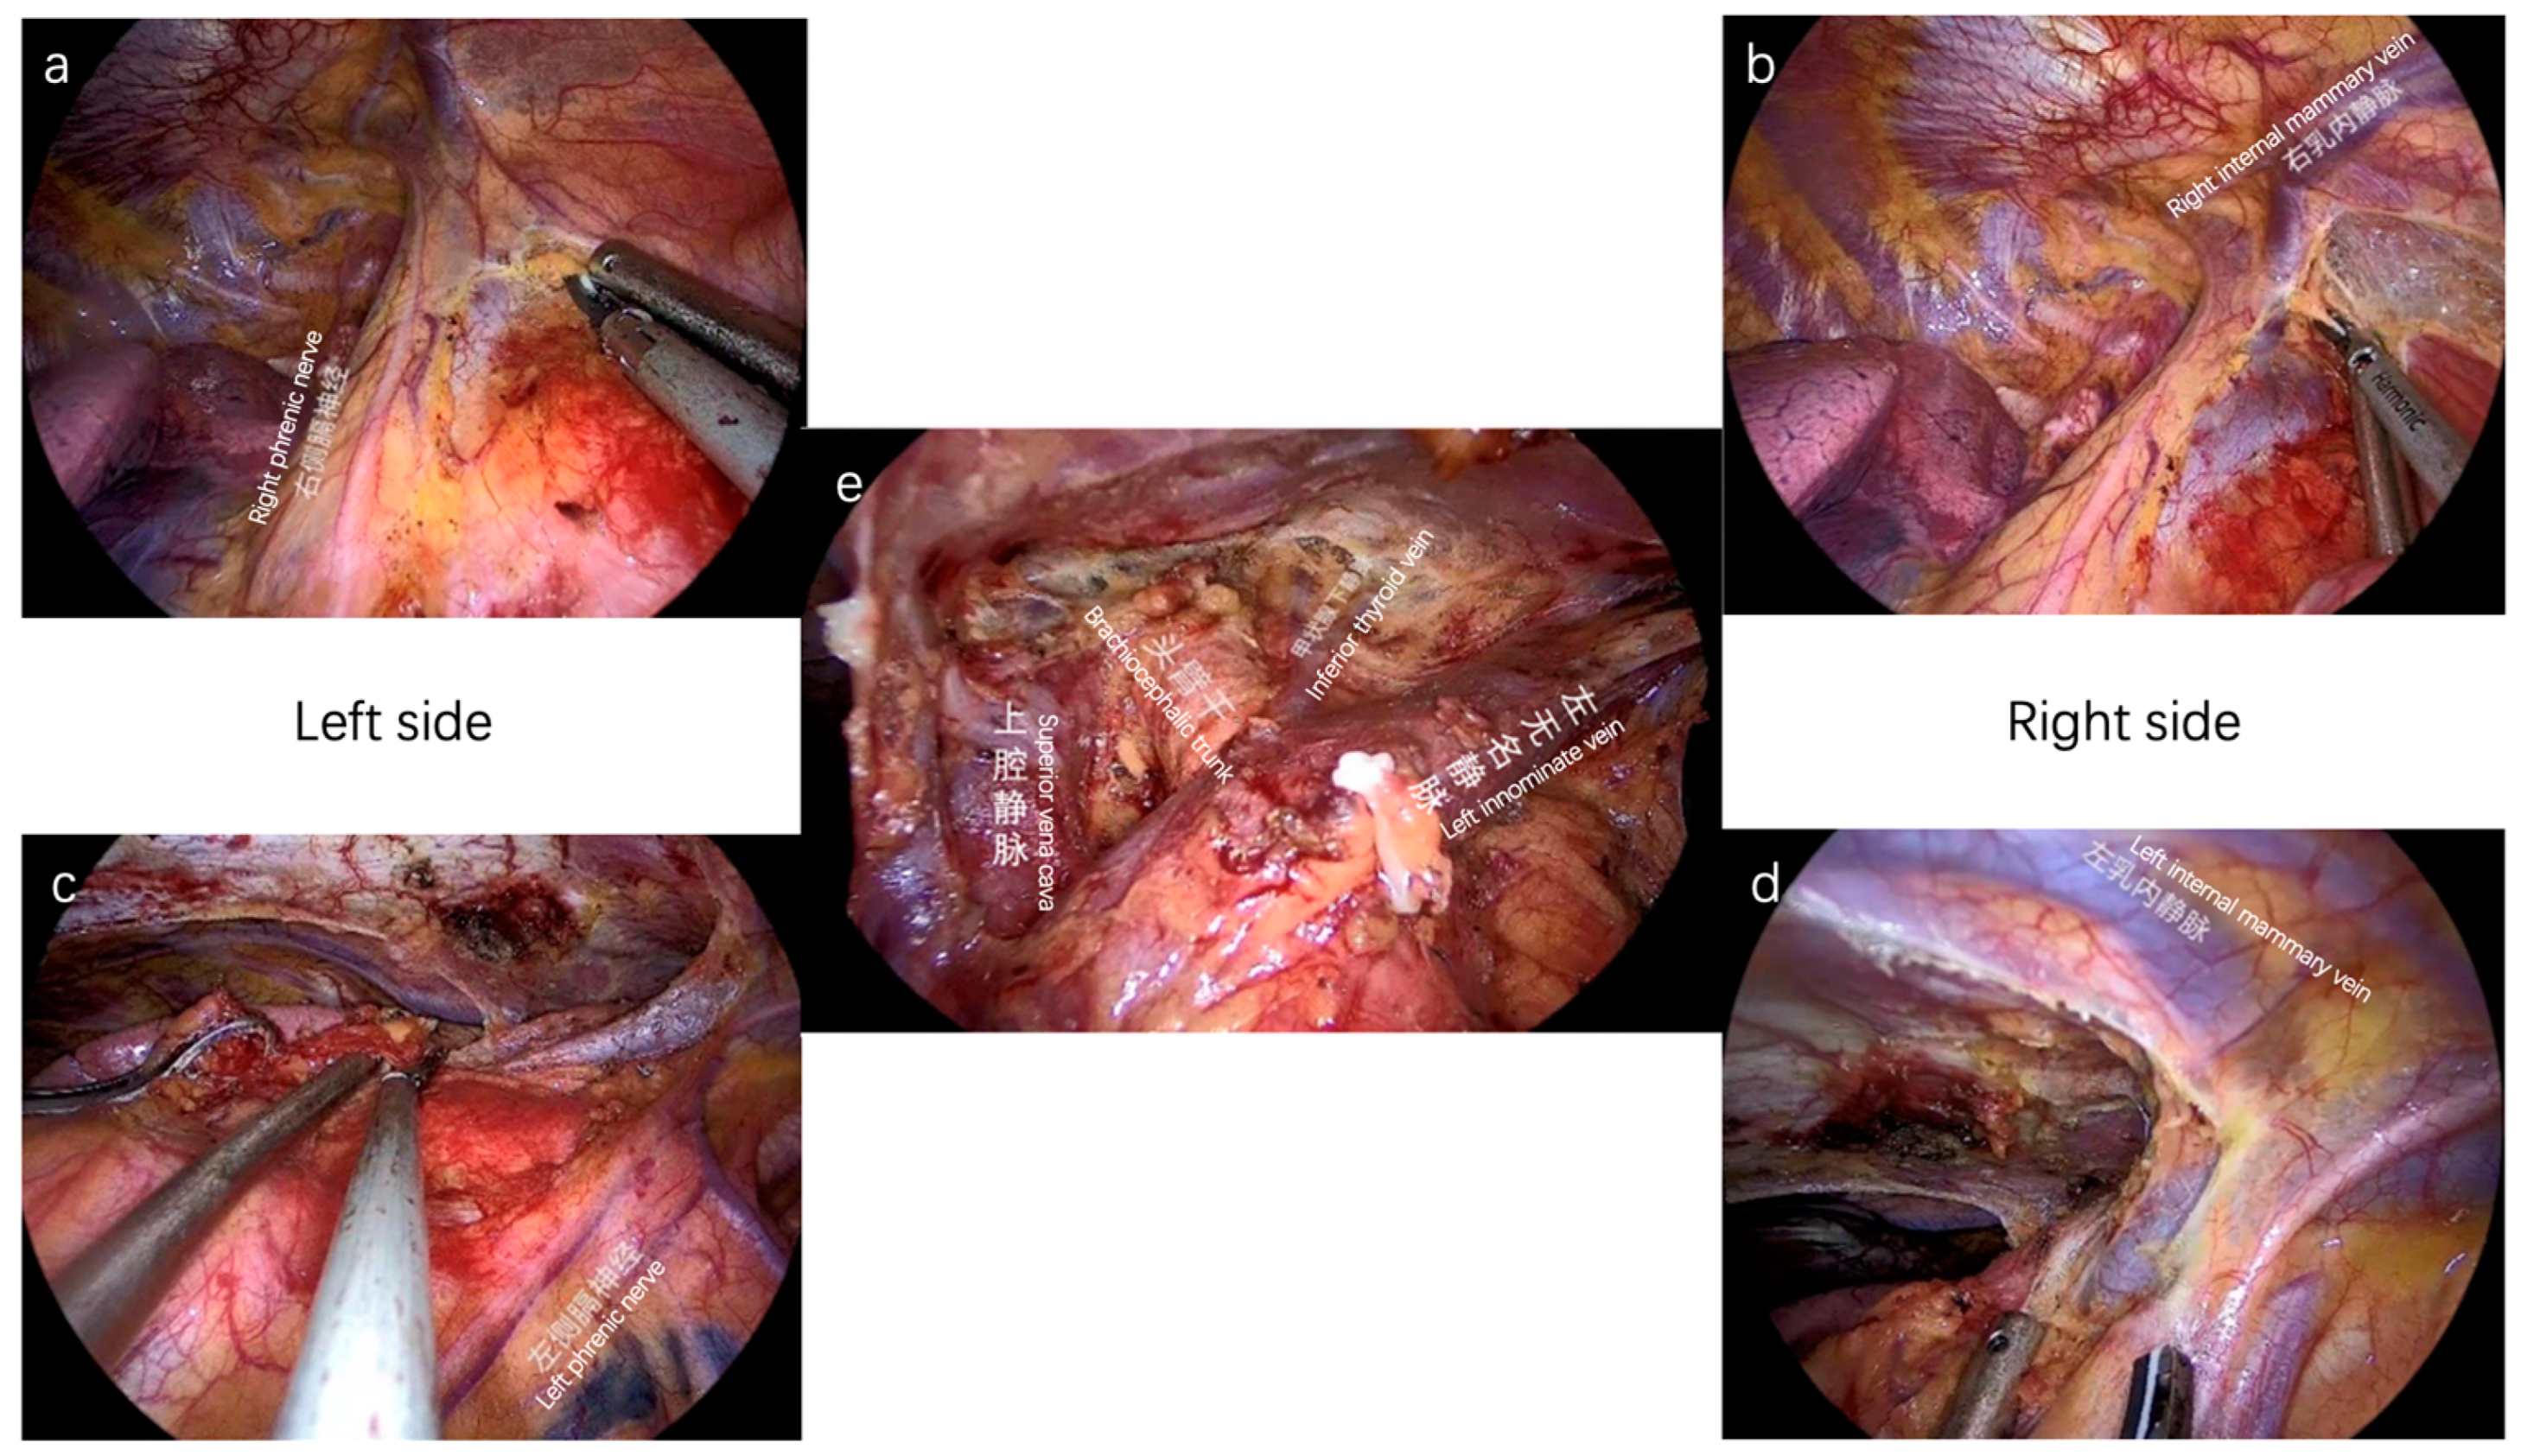

- Wang, X.; Aramini, B.; Xu, H.; Fan, J. Thymectomy with angioplasty through a thoracoscopic subxiphoid approach with double elevation of the sternum in Masaoka stage III thymoma. JTCVS Tech. 2021, 8, 208–210. [Google Scholar] [CrossRef]

- Jiang, J.H.; Gao, J.; Zhang, Y.; Wang, H.; Tan, L.J.; Ding, J.Y. Modified Subxiphoid Thoracoscopic Thymectomy for Locally Invasive Thymoma. Ann. Thorac. Surg. 2021, 112, 1095–1100. [Google Scholar] [CrossRef]

- Wang, X.; Aramini, B.; Zhu, Y.; Jiang, G.; Fan, J. Management of bleeding complications during thymectomy by subxiphoid approach with double elevation of the sternum: A case report. Mediastinum 2021, 5, 10. [Google Scholar] [CrossRef]